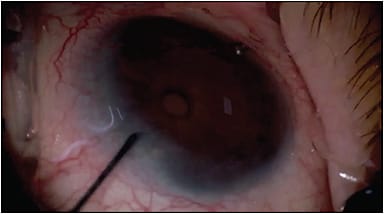

The Cypass Micro-Stent (Alcon Laboratories) is a suprachoroidal device that was approved for use in the United States in 2016 (Figure 2). It is indicated for implantation in combination with cataract surgery for the reduction IOP in eyes with mild to moderate POAG and visually significant cataract. The Cypass implant is a fenestrated microstent made from biocompatible polyimide material, which is designed to facilitate suprachoroidal aqueous outflow once inserted into the supraciliary space. Following its insertion with a curved guidewire, the Cypass bends to follow the scleral contour along the supraciliary space. The stent’s inherent stiffness and a series of retention rings at its proximal end secure the stent within the angle and the supraciliary space. As an ab interno, minimally invasive procedure, the Cypass Micro-Stent was intended to be less traumatic than full-thickness penetration procedures and easier to implant.8